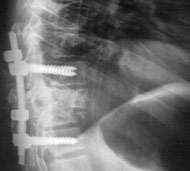

- Операція. Часто необхідно проведення термінової операції, щоб видалити фрагменти кісток, сторонні тіла, грижу міжхребцевого диска або зламані фрагменти хребця, що здавлюють вміст хребетного каналу. Операція також може знадобитися для стабілізації хребта, щоб запобігти появі болю або деформації. Існують деякі протиріччя щодо кращого часу проведення операції. Деякі хірурги вважають, що її необхідно виконувати раніше, інші вважають, що безпечніше почекати кілька днів до проведення будь-якої операції. Науково обгрунтованих доказів переваг ранніх (ургентних) операцій не отримано.

Мета операції - стабілізація хребта металевими конструкціями (імплантантами). Наша клініка була першою в СНД, яка застосувала сучасні конструкції при переломах хребта. Нині ми використовуємо імпортні конструкції типу CD Horison Legacy (США), Atlantis (США), Sextant (США), Socore (Франція). Операції вимагають складної рентгенівської техніки та спеціального інструментарію. При неускладнених переломах хребта хворі можуть ходити після таких операцій уже на другий - третій день. Також в Міжнародному центрі нейрохіургіі вперше в Україні впроваджено метод мініінвазивних операцій при переломах хребта.